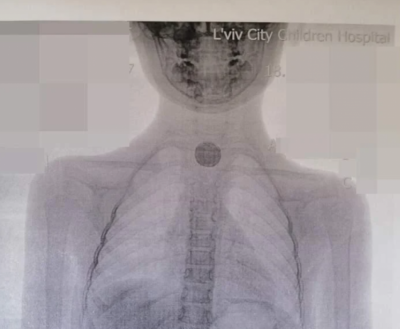

"У Львівській міській дитячій лікарні дівчинці зробили рентген і направили зі знімком до нас, в ОХМАТДИТ. На знімку видно було в стравоході чужорідне тіло круглої форми. 11 липня ми прооперували дівчинку. Коли зайшли в стравохід, то зрозуміли, що вона проковтнула не монету, а батарейку: там було все чорне і обпалене", - розповів Колодій.

З стравоходу дитини дістали батарейку розміром з 25 копійок. Пристрій спровокував у дівчинки великий набряк і опік стравоходу.